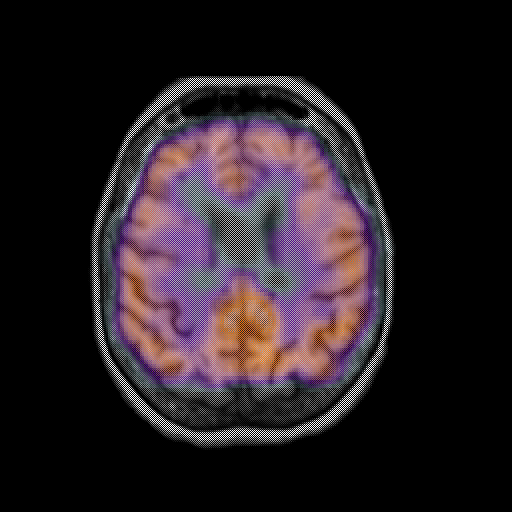

overlay: Slice 36

Slice 36

MRCBFCBF with

T1PDT2T1PDT2